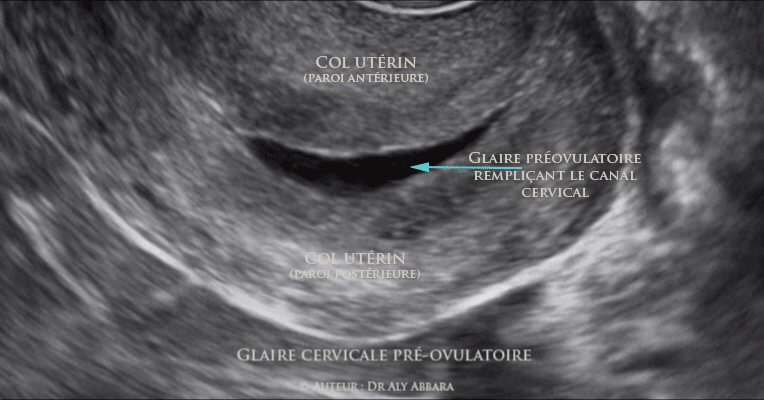

Glaire endocervicale en période pré-ovulatoire

Utérus : la glaire cervicale de la phase pré-ovulatoire est identifiable en échographie : structure anéchogène remplissant et élégissant le canal endocervical.

Cette séquence vidéo est associée aux autres signes échographiques de la période pré-ovulatoire : endomètre en phase proliférative avancée ; ovaire droit contenant un follicule dominant de 22 mm de grand axe ; cliniquement l'orifice externe du col utérin était béante, la glaire endocervicale était abondante se déversant en fontaine ; elle était également transparente (eau de roche) et très filante.